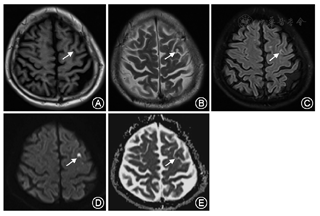

患者男性,65岁,以"右侧肢体不自主运动3 d"为主诉于2017年5月20日入我院。患者3 d前无明显诱因出现右侧肢体无意识、不规则的画图样运动,其特点为臂内旋、肘膝关节屈曲、足背屈样偏身不自主运动,鼻唇沟变浅,额纹未消失,右上肢麻木,紧张感。既往有高血压病史10余年,血压最高达160/90 mmHg(1 mmHg=0.133 kPa);否认吸烟饮酒史以及毒物接触史,否认糖尿病史以及神经变性疾病的家族史。神经系统体检示:意识清楚,语言流利,反应灵敏,双侧瞳孔等大同圆,对光反射灵敏,颈强直阴性;四肢肌力正常,足底略屈曲,左侧肢体肌张力正常,右侧肢体肌张力减弱;双侧肱二头肌、肱三头肌反射正常,双侧膝腱、跟腱反射正常,双侧巴宾斯基征、双侧霍夫曼征未引出;振动觉、位置觉、轻触觉、痛觉等未见明显异常。实验室检查结果:血清甘油三酯2.36 mmol/L(正常值0~1.70 mmol/L),血清总胆固醇6.91 mmol/L(正常值0~5.72 mmol/L),血糖、血清电解质、尿糖、尿酮体、铜蓝蛋白及甲状旁腺激素等均未见明显异常。颅脑CT平扫(64排)未见明显异常。胸片及心电图示无明显异常。颅脑MRI示:左侧额中回类圆形长T1、长T2信号影;液体衰减反转恢复序列(FLAIR)高信号影(图1A~C)。弥散加权成像(DWI)示左侧额中回皮质区类圆形极高信号影,表观弥散系数(ADC)在同一位置呈低信号影(图1D、图1E);提示该患者左侧额叶急性梗死。同时,基底神经节、丘脑以及丘脑底核未见异常信号影(图2)。因此给予患者改善循环、营养神经、联合抗血小板、降脂稳定斑块等综合治疗,另给予患者氯硝西泮0.5 mg,3次/d,口服;硫必利50 mg,3次/d,口服。出院2个月后随访,患者不自主运动,鼻唇沟变浅等症状消失,且未出现额外的非自主运动,右侧肢体麻木、紧张感缓解。